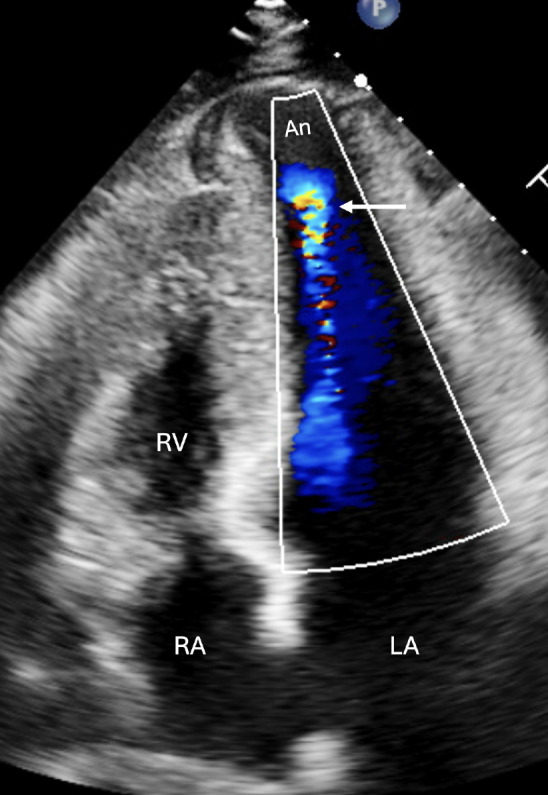

Mid-ventricular hypertrophic cardiomyopathy is a rare subgroup within hypertrophic cardiomyopathies that may present with apical aneurysm. This condition is associated with an increased risk of cardiac adverse events, including cardiac arrest, heart failure, thromboembolic events, or sudden cardiac death. We present a case of a 41-year-old man who presented with a history of exertional dyspnea and syncope. Multimodality imaging with echocardiography and cardiac magnetic resonance showed hypertrophy of the mid-ventricular segments with apical aneurysm. An implantable cardioverter-defibrillator was implanted to prevent sudden cardiac death.